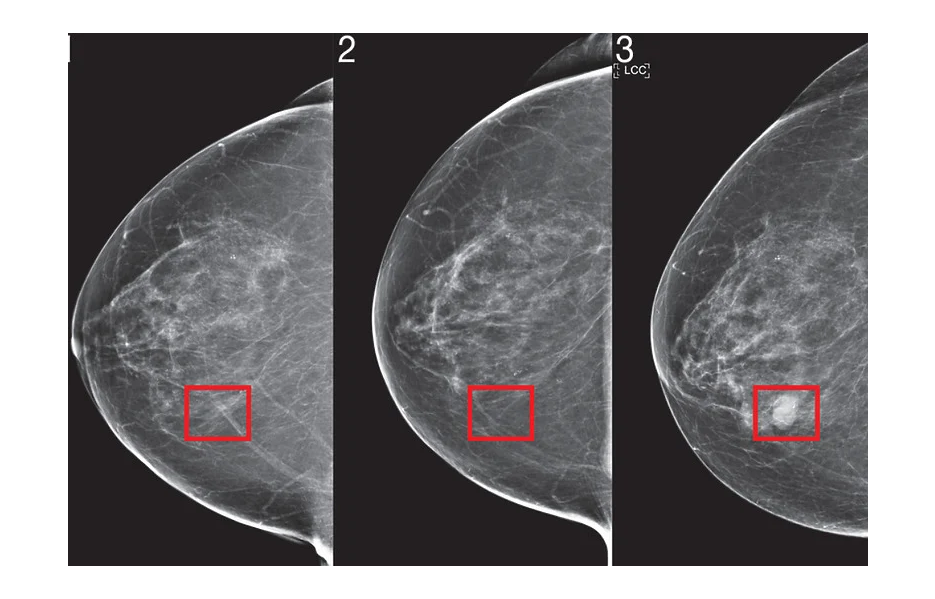

MIT je koristio umjetnu inteligenciju kako bi predvidio razvoj raka dojke. Na fotografijama modela koje proizvodi moguće je vidjeti dio tkiva koji je identificiran kao područje visokog rizika koji je četiri godine kasnije prerastao u karcinom.

Foto: MIT